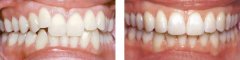

孩子前牙拥挤有危害吗?

前牙拥挤在牙颌畸形中是较为常见的。前牙拥挤的原因主要是颌骨前部发育不足...【详细】

牙齿拥挤要怎么修复?

牙齿拥挤是常见的错合畸形,表现为牙齿拥挤错位排列不齐;而拥挤牙齿的龋及...【详细】

矫正牙齿拥挤需要拔牙吗?

牙齿拥挤是患者内心的一块石头,严重影响外观,还会影响身体健康,很多人因...【详细】